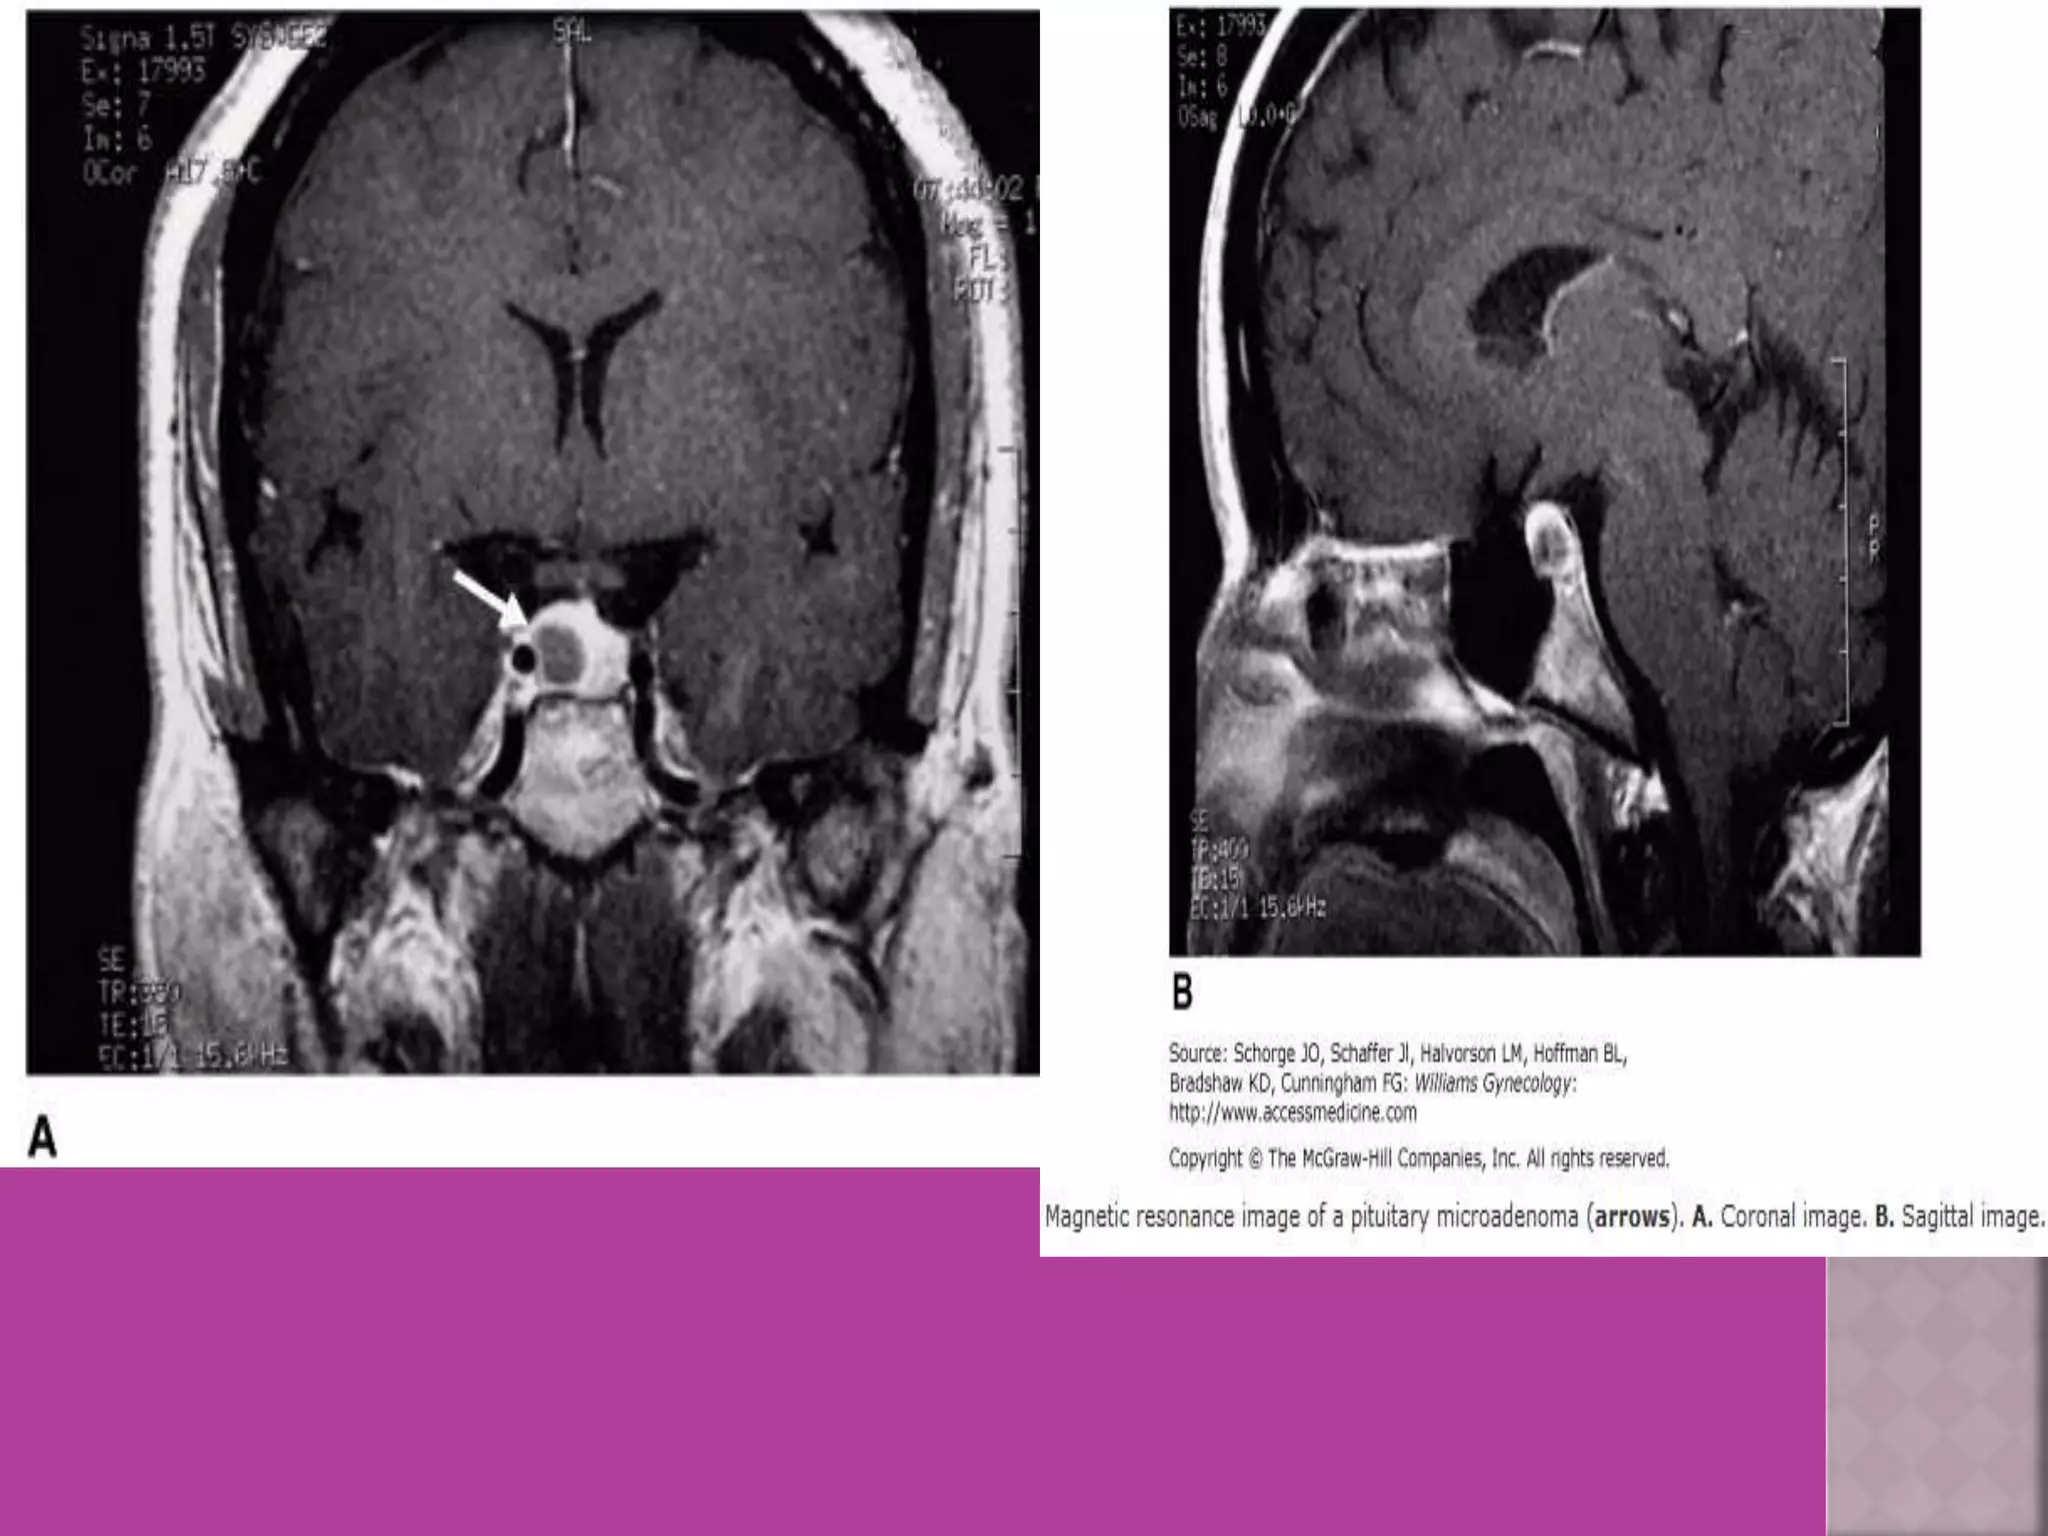

MRI---Pituitary adenoma (A) MRI– Pituitary fosa after surgery of

macroadenoma

empty

Fosa

MRI---Pituitary adenoma (A)MRI– Pituitary fosa after surgery of macroadenoma empty Fosa